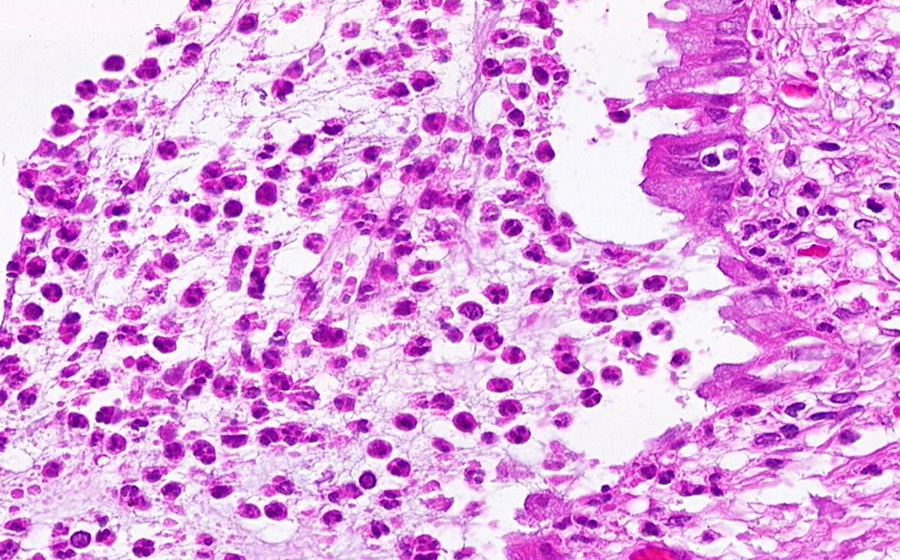

Slide 3: Chronic cervicitis and metaplasia

Histologic section of cervix from a patient with chronic cervicitis (click here to review normal tissue)

Image 3 - 100X

Slide 3 - Image 3